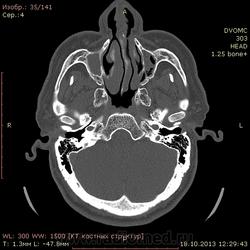

72 года. Жалобы на частые головные боли. В мозгах вроде ничего особенного, а вот пазухи...лобной нет, клиновидная недоразвитая. Вопрос вот какой:

Можно ли считать картину в, опять таки недоразвитых, верхнечелюстных пазухах (особенно слева) как хронический гайморит?(или острый такой бывает?) вся эта неоднородность и полости воздушные и мягкотканная плотность....

Написал бы как дополнение: двусторонее нарушение пневматизации в обеих в/ч, справа тотальное, слева субтотальное вспененными плотностями. Синусит? в правой в/ч возможно, полипозный (или кистознополипозный, как вам больше нравится). Рек. конс. ЛОР.